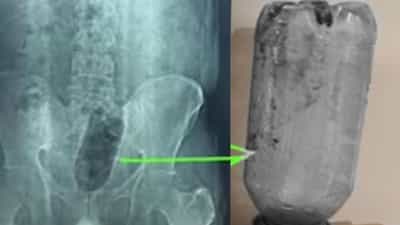

युवक के निजी अंग में फंसी बोतल Image Credit:

मामला आगरा में शाहगंज थाना क्षेत्र का है. साकेत कॉलोनी स्थित नवदीप हॉस्पिटल के डॉक्टरों के मुताबिक चार दिन पहले पहले एक युवक दर्द से कराहते हुए आया था. उसकी हालत देखकर डॉक्टर ने एक्सरे कराया. इसमें पता चला कि युवक के मलाशय में एक लीटर पानी की प्लास्टिक बोतल फंसी हुई है. अस्पताल के डॉयरेक्टर एवं वरिष्ठ सर्जन डॉ. सुनील शर्मा के मुताबिक ऐसे में सिग्मोइंडोस्कोपी कराई गई तो पता चला कि मलाशय में गहरे घाव भी हैं, जिसकी वजह से वह शौच भी नहीं कर पा रहा.

डॉ. सुनील शर्मा के मुताबिक युवक साइको सेक्सुअल डिसऑर्डर एनल इरोटिजम (गुदा कामुकता) नामक बीमारी से ग्रसित है. ऐसे मरीजों को गुदा स्पर्श करने में आनंद की अनुभूति होती है. इसकी वजह से वह अपने निजी अंग में कोई भी चीज डाल लेते हैं. 38 साल के इस युवक ने भी इसी तरीके से आनंद प्राप्त करने की कोशिश की, लेकिन बोतल उसकी गुदा में ही फंस गई. जब दर्द काफी बढ़ गया तो 36 घंटे बाद ऑपरेशन कर गुदा से बोतल को बाहर निकाला गया है. उन्होंने बताया कि इसके लिए करीब 75 मिनट तक ऑपरेशन चला.